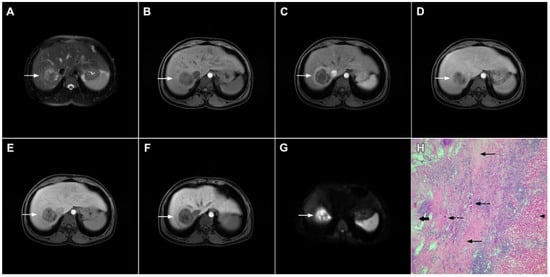

Mucinous cholangiocarcinoma is a rare variant of mICC characterized by rich mucin production [24,27]. According to previous studies, mucinous mICC originate from mucin-producing cholangiocytes located in large bile ducts [28]. Imaging findings in mucinous mICC reflect characteristic histopathological features of the lesion with cancer cell nests suspended in a large mucinous lake [29]. Therefore, these lesions display strong T2-weighted hyperintensity [27]. Moreover, as cancer cells in the center of the lesion are scarce, these tumors show only slight progressive enhancement of intralesional septa and cellular nests in postcontrast studies (Figure 7) [27]. Due to its very high signal intensity on T2-weighted images and centripetal pattern of enhancement, mucinous mICC may be misdiagnosed as hemangiomas [29]. Concerning similarities in the postcontrast behavior of mucinous mICC and hemangiomas, it should be kept in mind that mICC displays continuous ragged rim enhancements in contrast to the discontinuous, stronger peripheral and centripetal enhancement following the blood pool seen in hemangiomas [24,29].

Figure 7.

Mucin-rich mass-forming cholangiocarcinoma in a 78-year-old woman. The axial T2-weighted image (A) shows the lobulated hyperintense lesion (arrow) located in the subcapsular region of liver segment IVB, which is associated with capsular retraction. On the plain T1-weighted image (B) the lesion (arrow) is hypointense. In the arterial phase (C), ring enhancement can be seen with slight “ragged” central enhancement in the portal venous (D) and delayed phase (E). On DWI, diffusion restriction is noted on the periphery of the lesion (arrow) while no restriction is seen in the central part of the tumor (F). Corresponding ADC map showing targetoid appearance of the lesion is shown on (G). Hematoxylin and eosin (H&E) staining (H) showed cholangiocarcinoma (arrows) adjacent to normal liver parenchyma (dashed arrow); original magnification ×40.